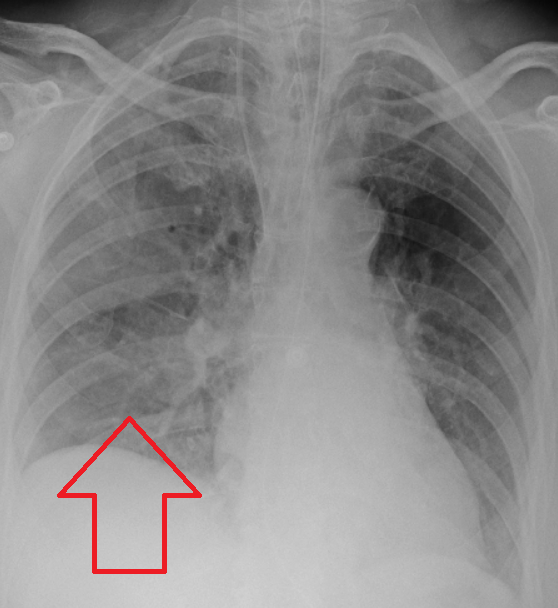

흡인성 폐렴은 일반적으로 임상적 상황(흡인 위험 요소가 있는 사람)과 방사선학적 소견(적절한 위치의 침윤)의 조합으로 진단된다.[2] 흡인성 폐렴을 포함하여 폐렴이 의심되는 경우 일반적으로 흉부 X선 검사를 시행한다. 흉부 X선 소견에서 흡인성 폐렴을 뒷받침하는 소견에는 환자가 흡인이 발생했을 때의 자세에 따라 국소적인 실변이 포함된다. 예를 들어, 앙와위로 흡인된 사람은 종종 폐의 우하엽에 실변이 생긴다. 오염 위험이 높기 때문에 객담 배양은 흡인성 폐렴 진단에 사용되지 않는다. 흡인 후 호흡 곤란과 발열과 같은 임상 증상도 흡인성 폐렴에 대한 의심을 증가시킬 수 있다. 마찬가지로, 영향을 받은 폐 영역에서 들리는 변화된 호흡음과 같은 신체 검사 소견도 흡인성 폐렴을 시사할 수 있다. 일부 흡인성 폐렴의 경우는 음식 입자 또는 알약 조각과 같은 기타 미립자 물질의 흡인으로 인해 발생하며, 이는 폐 생검 검체에서 병리학자에 의해 진단될 수 있다.[15]